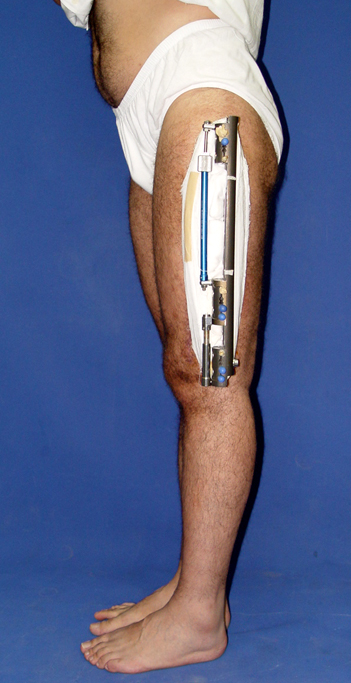

Kırık kaynama yokluklannın tedavisi hala, ortopedik cerrah için çözümü güç sorunlardandır. Tek bir tedavi yöntemi yoktur. Tüm bu yöntemler problemli ve daima komplikasyonlara açıktır. Kaynamamaya enfeksiyon, yumuşak doku kaybı ile deformite ve kısalık eşlik edebilmektedir, Kaynamama için internal ve eksternal birçok teknik belirtilmiştir. Kaynamayan kemik uçlarının çıkartılması, damarlı fibula veya fibula grefti, damarlı kas greftleri ile birlikte internal fiksasyon uygulamaları, elektrik stimulasyon gibi uygulamalar kaynamamada bir şeçenektir. Fakat kısalık ve deformite gibi ek patolojiler tedavisinde kısıtlı kalmaktadır. İlizarov eksternal fiksatörü ile uygulanan distraksiyon osteogenezi uygulamaları ile birlikte yapılan psödoartroz sahasından akut kısatma ve aynı kemikteki diğer segmentten uzatma yapılmaktadır. Ilizarov ve arkadasları, kendi geliştirdikleri yöntem ve fiksatörle, aynı anda, hastanın günlük aktivitelerini kısıtlamadan, eklem fonksiyonlarını koruyarak kaynamayı basarmıs,deformiteyi düzeltmis, uzunlugu yeniden sağlamıstır. Bu teknik sayesinde kemik defektlerinin kapatılması ve enfeksiyon gibi hastaya morbidite getiren ek patolojiler giderilmiş aynı zamanda kısalıkta telafi edilmiştir.